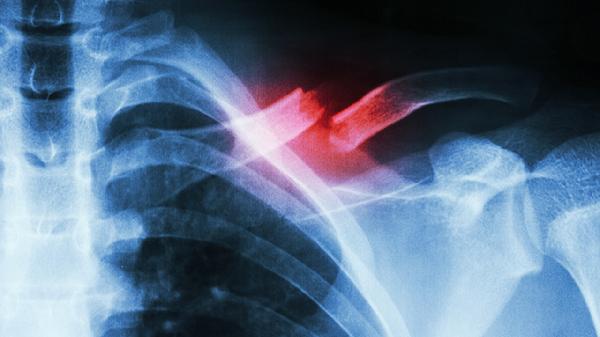

肋骨骨折起床时需采用侧身支撑法,避免直接仰卧起坐或扭转身体。肋骨骨折多由外伤、骨质疏松等因素引起,可能伴随胸痛、呼吸受限等症状。